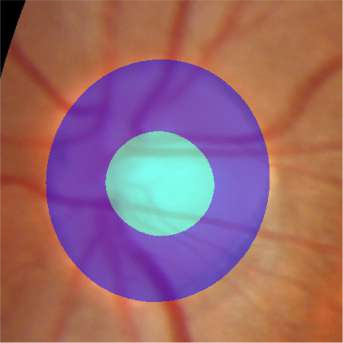

Glaucoma is the second leading cause of blindness and is the leading cause of irreversible blindness disease in the world. Early screening for glaucoma in the population is significant. Color fundus photography is the most cost effective imaging modality to screen for ocular diseases. Deep learning network is often used in color fundus image analysis due to its powful feature extraction capability. However, the model training of deep learning method needs a large amount of data, and the distribution of data should be abundant for the robustness of model performance. To promote the research of deep learning in color fundus photography and help researchers further explore the clinical application signification of AI technology, we held a REFUGE2 challenge. This challenge released 2,000 color fundus images of four models, including Zeiss, Canon, Kowa and Topcon, which can validate the stabilization and generalization of algorithms on multi-domain. Moreover, three sub-tasks were designed in the challenge, including glaucoma classification, cup/optic disc segmentation, and macular fovea localization. These sub-tasks technically cover the three main problems of computer vision and clinicly cover the main researchs of glaucoma diagnosis. Over 1,300 international competitors joined the REFUGE2 challenge, 134 teams submitted more than 3,000 valid preliminary results, and 22 teams reached the final. This article summarizes the methods of some of the finalists and analyzes their results. In particular, we observed that the teams using domain adaptation strategies had high and robust performance on the dataset with multi-domain. This indicates that UDA and other multi-domain related researches will be the trend of deep learning field in the future, and our REFUGE2 datasets will play an important role in these researches.